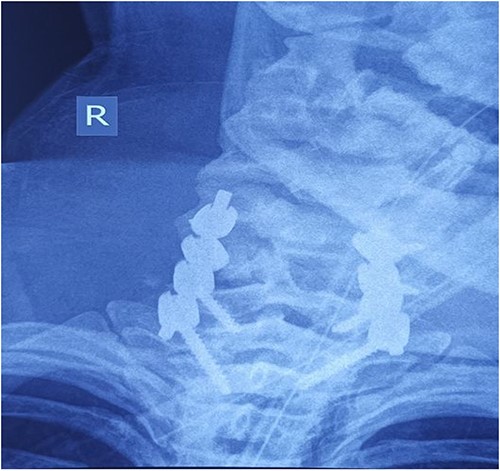

On the fourth day after the injury, the patient was conscious, on low doses of vasopressor support. What was surprising was that in her conscious state she had weakened abduction of the left shoulder, while the right arm and legs were completely plegic (ASIA A). We decided to perform posterior reduction and stabilization from the level of C5 to T1 (Figs 3–5). On the first postoperative day, a follow-up X-ray of the cervical spine was performed (Figs 6 and 7).

Intraoperative finding after repositioning and stabilization: screws placed into the C5-C7 massae laterales and the T1 pedicles; fixation performed with titanium rods.

Cervical spine X-ray postoperatively – AP view: properly positioned osteosynthesis material.